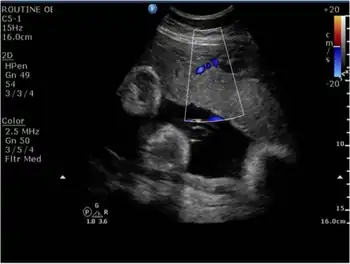

In terms of the diagnosis of Intrauterine growth restriction, the use of ultrasound is essential[25]